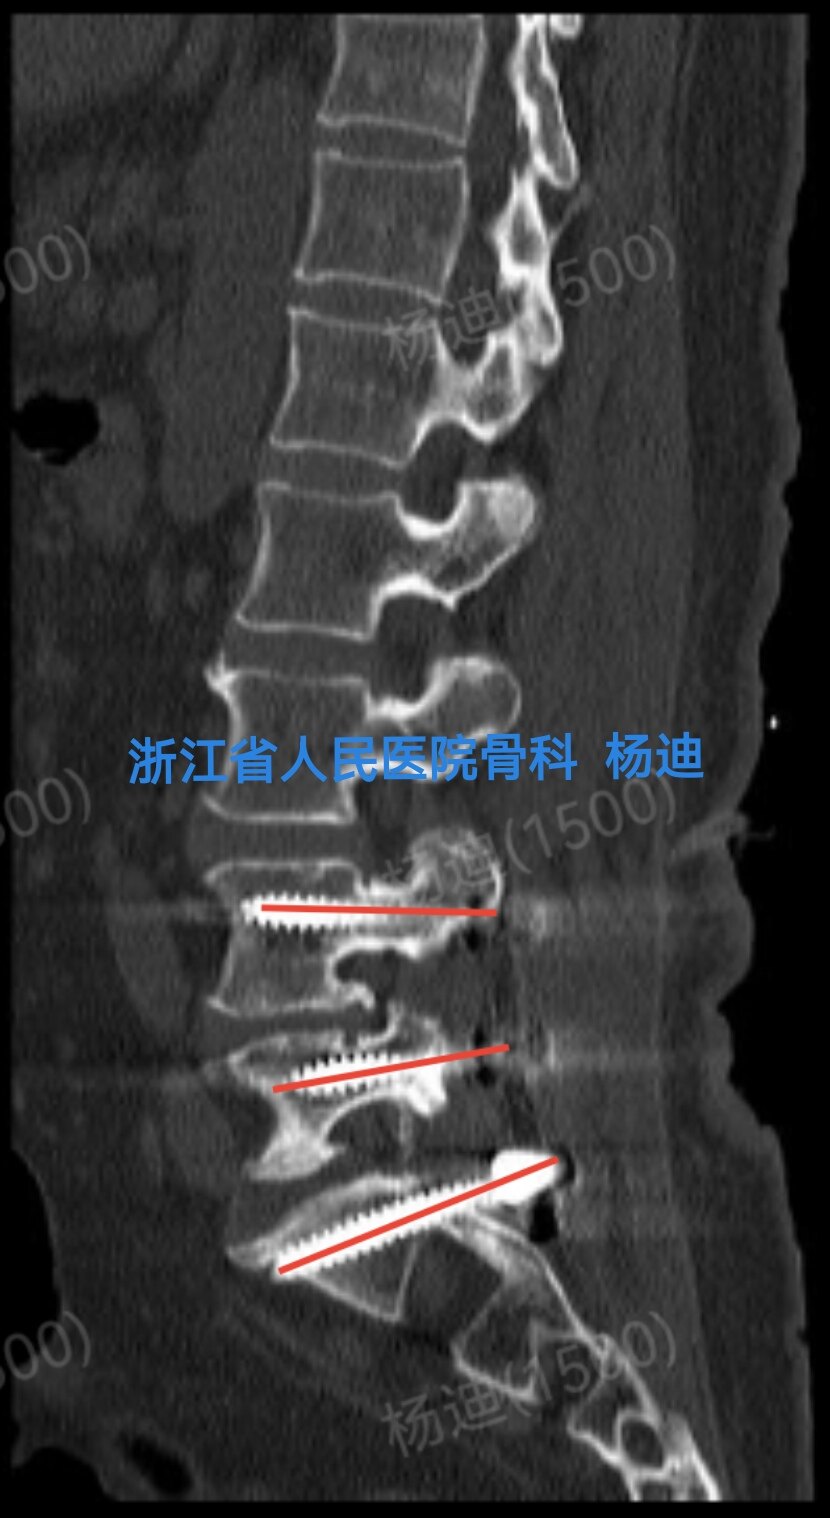

图为术后腰椎CT矢状位重建,提示左侧腰4、腰5、骶1螺钉位置及长度满意(红色直线)。

图为术后腰椎CT矢状位重建,提示右侧腰4、腰5、骶1螺钉位置及长度满意(红色直线)。

图为术后腰椎CT矢状位重建:椎间隙高度恢复(橙色直线间距离),融合器位置良好,植骨充分(红色箭头)。

图为术后腰椎CT矢状位重建:椎间隙高度恢复(橙色直线间距离),融合器位置良好,植骨充分(红色箭头)。